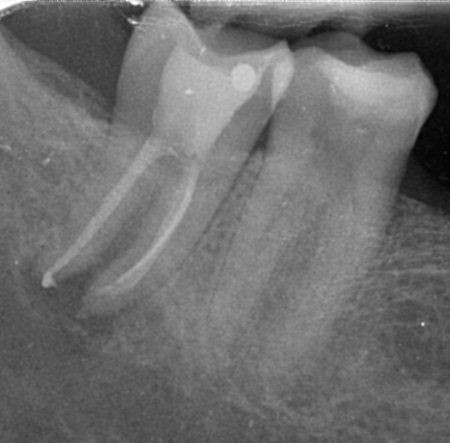

Trattamenti di endodonzia

L'endodonzia è quella branca dell'odontoiatria che si occupa della terapia dello spazio all'interno del dente che contiene la polpa dentaria, costituita da cellule, vasi e nervi. La terapia endodontica è indispensabile quando una lesione cariosa o traumatica al dente abbia determinato un'alterazione non reversibile del tessuto pulpare.

Presso lo studio Duchi, impieghiamo due tecniche endodontiche: la terapia ortograda, quando è possibile operare attraverso il dente lungo i canali radicolari (terapia canalare o devitalizzazione) e la terapia retrograda, più comunemente indicata come endodonzia chirurgica (apicectomia), per i casi in cui non è possibile passare lungo i canali radicolari, per la presenza di ostacoli di varia natura.

prima e dopo...